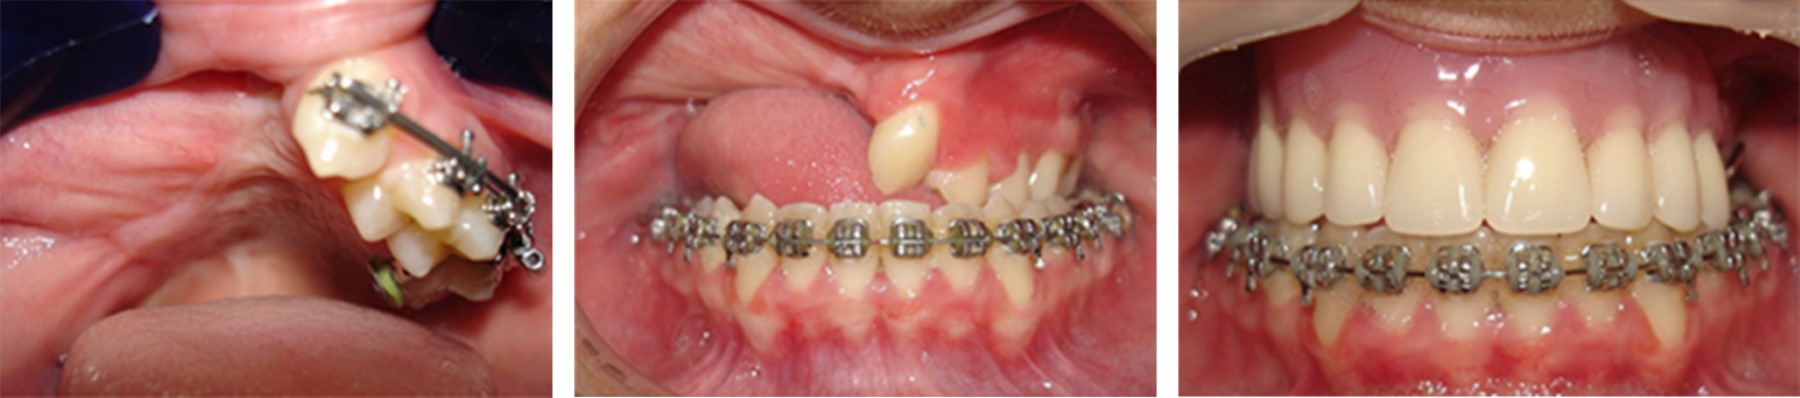

Juvenile trabecular ossifying fibroma maxillary with sarcomatization: 18-years follow-up

Ossifying fibroma a benign neoplasm of fibro-osseous tissue, with well-defined limits histologically characterized a large amount of fibrocellular and mineralized tissue. This pathology is classified two categories, including juvenile trabecular ossifying fibroma (TrOF) and psammomatoid (PsOF). Although the characteristics of these lesions are presented in a similar way, the great difference between them is the average age of presentation: 6-11.5 years the trabecular and from 12-18.9 years older the psammomatoid. Between these two groups there are histological variants and among them is the possible and unusual presentation of malignancy within the histology. The aim of this report is to describe the treatment of an eight-year-old female patient with a diagnosis of highly aggressive juvenile ossifying fibroma with points of possible sarcomatous transformation in maxillary without recurrences clinical, radiographic and tomographic follow-up for 18 years.